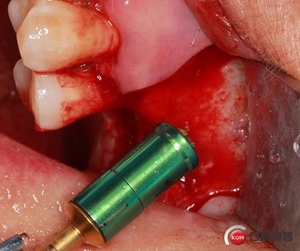

開孔鉆上安裝1mm停止環(huán)。

開窗位置鉆入1mm深度,未能穿透骨壁。

更換2mm停止環(huán)。

穿透上頜竇頰側(cè)骨壁,由于擴孔鉆鉆頭特殊的設(shè)計形態(tài)

轉(zhuǎn)速雖快但不會穿破上頜竇膜。

使用水壓系統(tǒng),將1ml左右生理鹽水緩慢注入開孔內(nèi)。